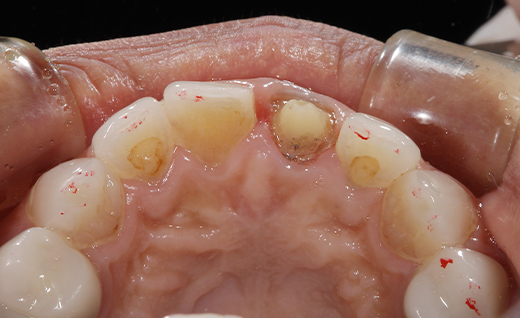

施術後

施術後コメント

治療後、鏡をご覧になった患者さまは、「わっ、すごく自然…!前歯ってこんなにきれいにできるんですね!」と笑顔に。 オールセラミックは金属を使わないため、自然な透け感や明るさがあり、まわりの歯ともよくなじみます。変色しにくく、美しさを長く保てるのも特徴です。 オールセラミッククラウンの費用は、1本あたり121,000円(税込)です。 前歯の変色や色の不揃いにお悩みの方、保険の被せ物からのアップグレードをご検討中の方は、ぜひ一度お気軽におかだ歯科クリニックへご相談ください。患者さまお一人おひとりに合ったご提案をさせていただきます。